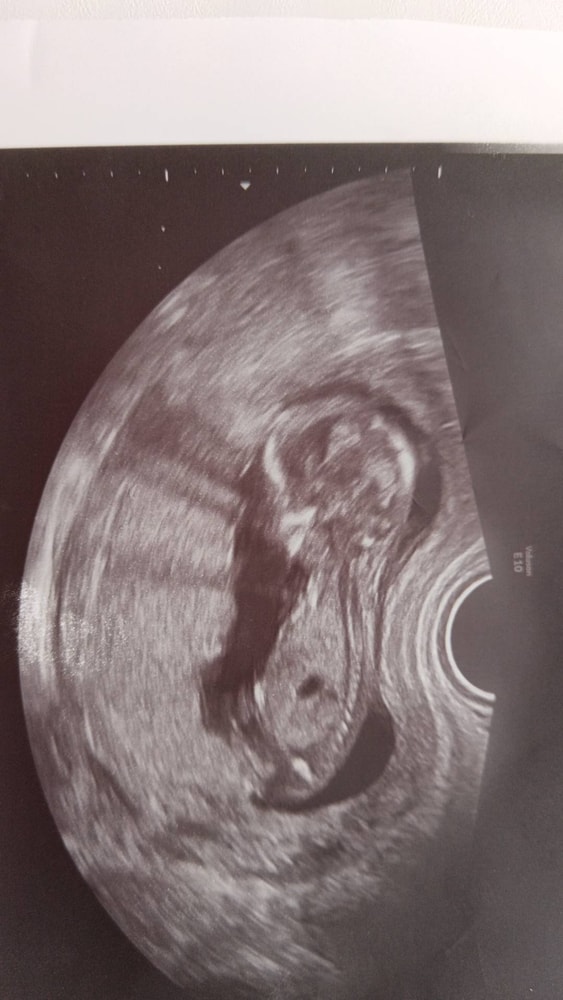

Абакумова Анна в Благополучная беременность 2 месяца Кто на узи, мальчик или девочка УЗИ, КТГ, доплер Кого вы видите? 😍 Посмотрите еще 20 записей на эту тему Отменить Ответить Ирина Понарошку А мне кажется мальчик.там как будто 🍌 торчит 09.10.2025 Ответить Анастасия На мальчишку похож) 09.10.2025 Ответить Виктория Плохо видно но скорее девочка 09.10.2025 Ответить Анютка А мне кажется мальчишка 09.10.2025 Ответить Я Девочка 09.10.2025 Ответить Мария Голосую за девочку! 09.10.2025 Ответить Вес плода в 30 недель Первое узи Чаты Беременных Выберите чат: Январята-2026 Февралята-2026 Мартята-2026 Апрелята-2026 Майчата-2026 Июнята-2026 Июлята-2026 Августята-2026